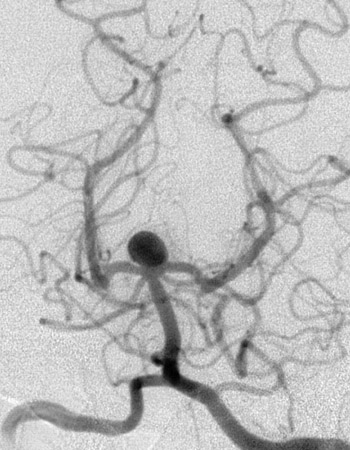

| This cerebral angiogram demonstrates a berry aneurysm jutting from the top of the basilar artery of the circle of Willis at the base of the brain. Berry aneurysms arise in a weak point in the arterial wall and generally become large enough to produce symptoms in adulthood. |